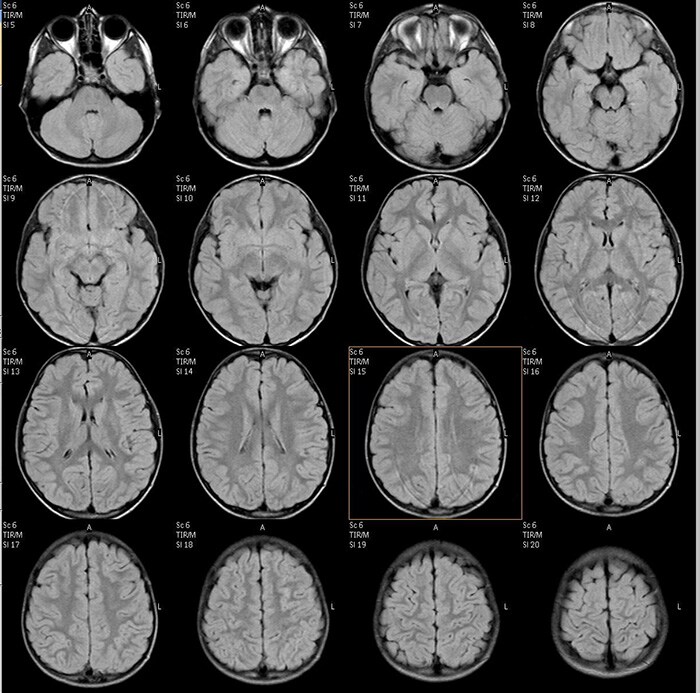

Рис. 3. МРТ данные пациента с ДЦП: на FLAIR изображениях структурные изменения минимальны.